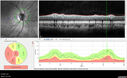

25 year old with AD optic atrophy. VA 20/80 OU. Her father also had vision loss and optic atrophy.

Autosomal Dominant Optic Atrophy - OPA1 Mutation145 views25 year old female with VA 20/80 OU and recent vision decline. Her father also has poor vision.00000

Autosomal Dominant Optic Atrophy - OPA1 Mutation163 views25 year old female with VA 20/80 OU and recent vision decline. Her father also has poor vision.00000

Autosomal Dominant Optic Atrophy - OPA1 Mutation161 views25 year old female with VA 20/80 OU and recent vision decline. Her father also has poor vision.00000